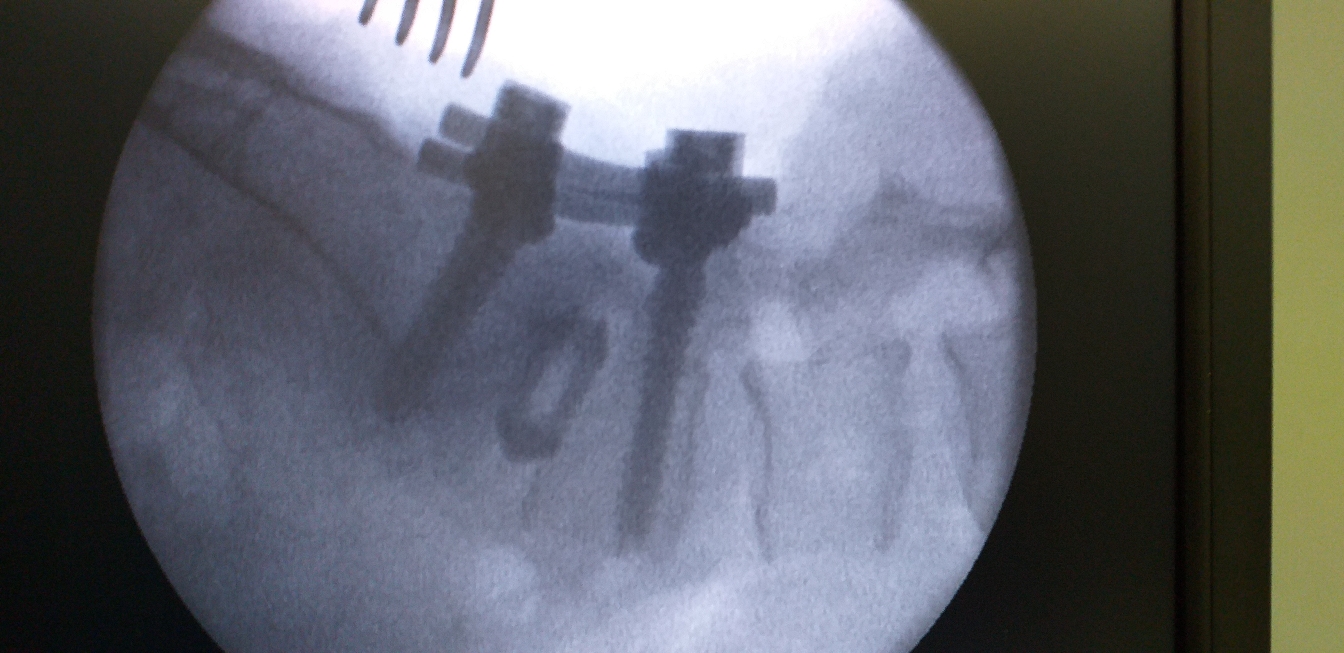

Revision Spine Surgery For Failed Spine Surgery